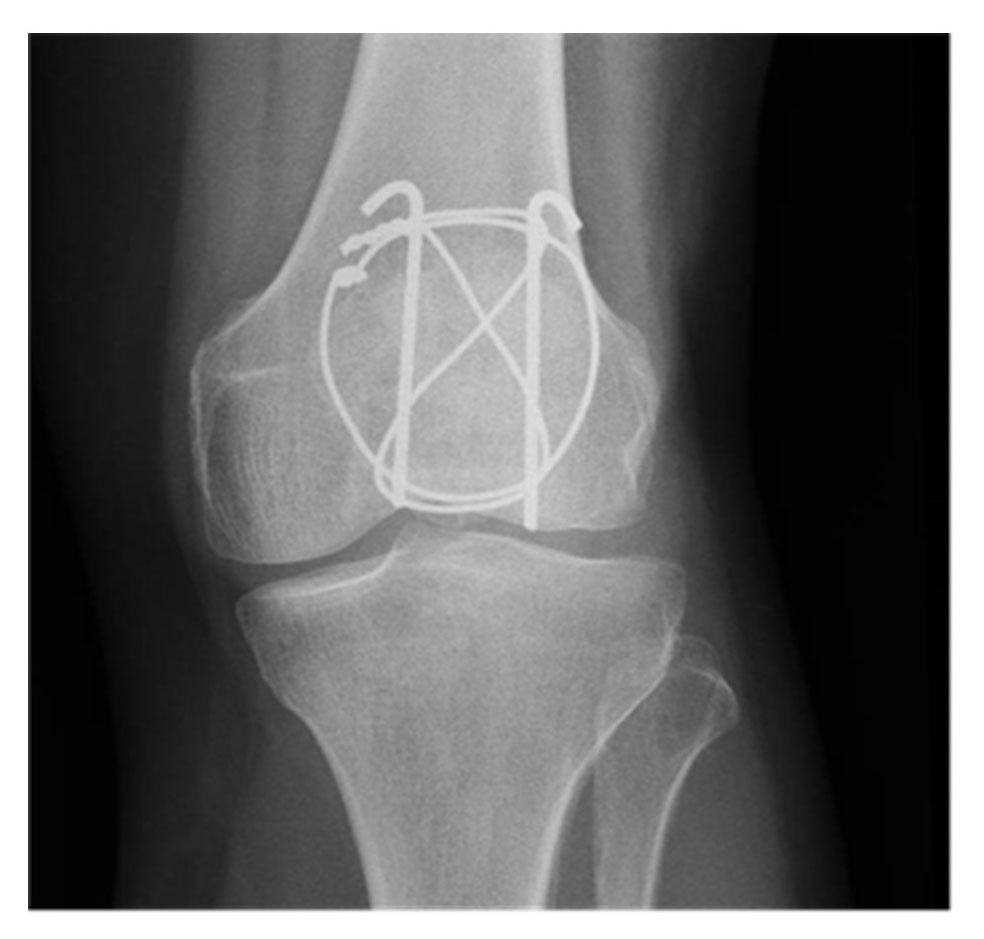

The technique developed in the 1950s by the Arbeitsgemeinschaft für Osteosynthesefragen / Association for the Study of Internal Fixation (AO/ASIF) for transverse fractures is ideal because it uses the compression of the braces during bending movements, which allows early mobilisation [13]. This technique converts the anterior tension forces produced by the extensor mechanism and knee flexion into compression forces at the articular surface (fig. 2). For maximum efficiency, there should be no loss of substance on the articular surface of the patella. Two parallel pins are inserted, then the brace is made of a metal wire that passes in front of the patella and then behind each pin by making a “figure of 8” (fig. 3). The pins are bent and depressed so as not to interfere with the soft tissues [14]. This technique gives good results in more than 80% of cases [15].

Figure 3 X-ray of a patella with tension band construct (CHUV).

The most commonly used method is a tension band technique; however, this is only possible after a more complex fracture has been converted into a two‐part fracture and if there is no discontinuity on the articular side. Additional fracture fragments can be fixed using supplementary circular wire (fig. 4) [16] or mini‐fragment screws (fig. 5) [17]. The repair of the retinacular defect contributes also to the overall stability of the construct.

Figure 4 Tension band construct reinforced with an equatorial wire (CHUV).